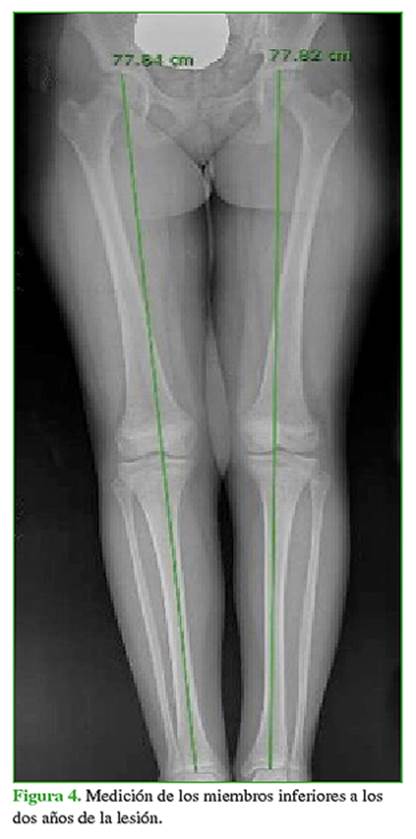

Se realizaron seguimientos mensuales con radiografías de rodilla y examen físico hasta completar seis meses desde la lesión, luego a los seis meses hasta los dos años posteriores a la lesión. No se apreciaron alteraciones en la fisis tibial proximal y no han aparecido alteraciones angulares en la rodilla, que se mantiene estable (Figura 4). Se mantendrán las revisiones anuales hasta que el paciente alcance la madurez esquelética para descartar alteraciones en el crecimiento.

Las complicaciones tardías pueden ser discrepancias de la longitud de los miembros y deformaciones axiales. En distintas series, se observa una diferencia de la longitud de los miembros >25 mm o desviación axial >5º en el 25% de los pacientes.14-16 Esto obedece a un cierre prematuro total o parcial de la placa de crecimiento (Hasler >30% de cierre precoz en su serie) o a la sobrestimulación de esta.17 Se debe realizar un seguimiento periódico con radiografías de ambos miembros completos para valorar si hay alteraciones e indicar medidas correctoras precoces. El seguimiento debe continuar hasta la osificación completa.